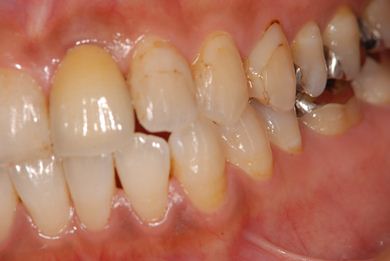

抜歯即日スピードインプラント治療

| 性別/年齢 | 女性 / 39歳 | ||||||||||||||||||||||||||||||||

| 主訴 | 左前歯の虫歯治療を希望。 | ||||||||||||||||||||||||||||||||

| 治療内容 | インプラント1本(抜歯即日スピードインプラント)、メタルボンドセラミック1本 | ||||||||||||||||||||||||||||||||

| 総治療費 | 458,588円 | ||||||||||||||||||||||||||||||||

| 治療期間 | 1年0ヶ月 |